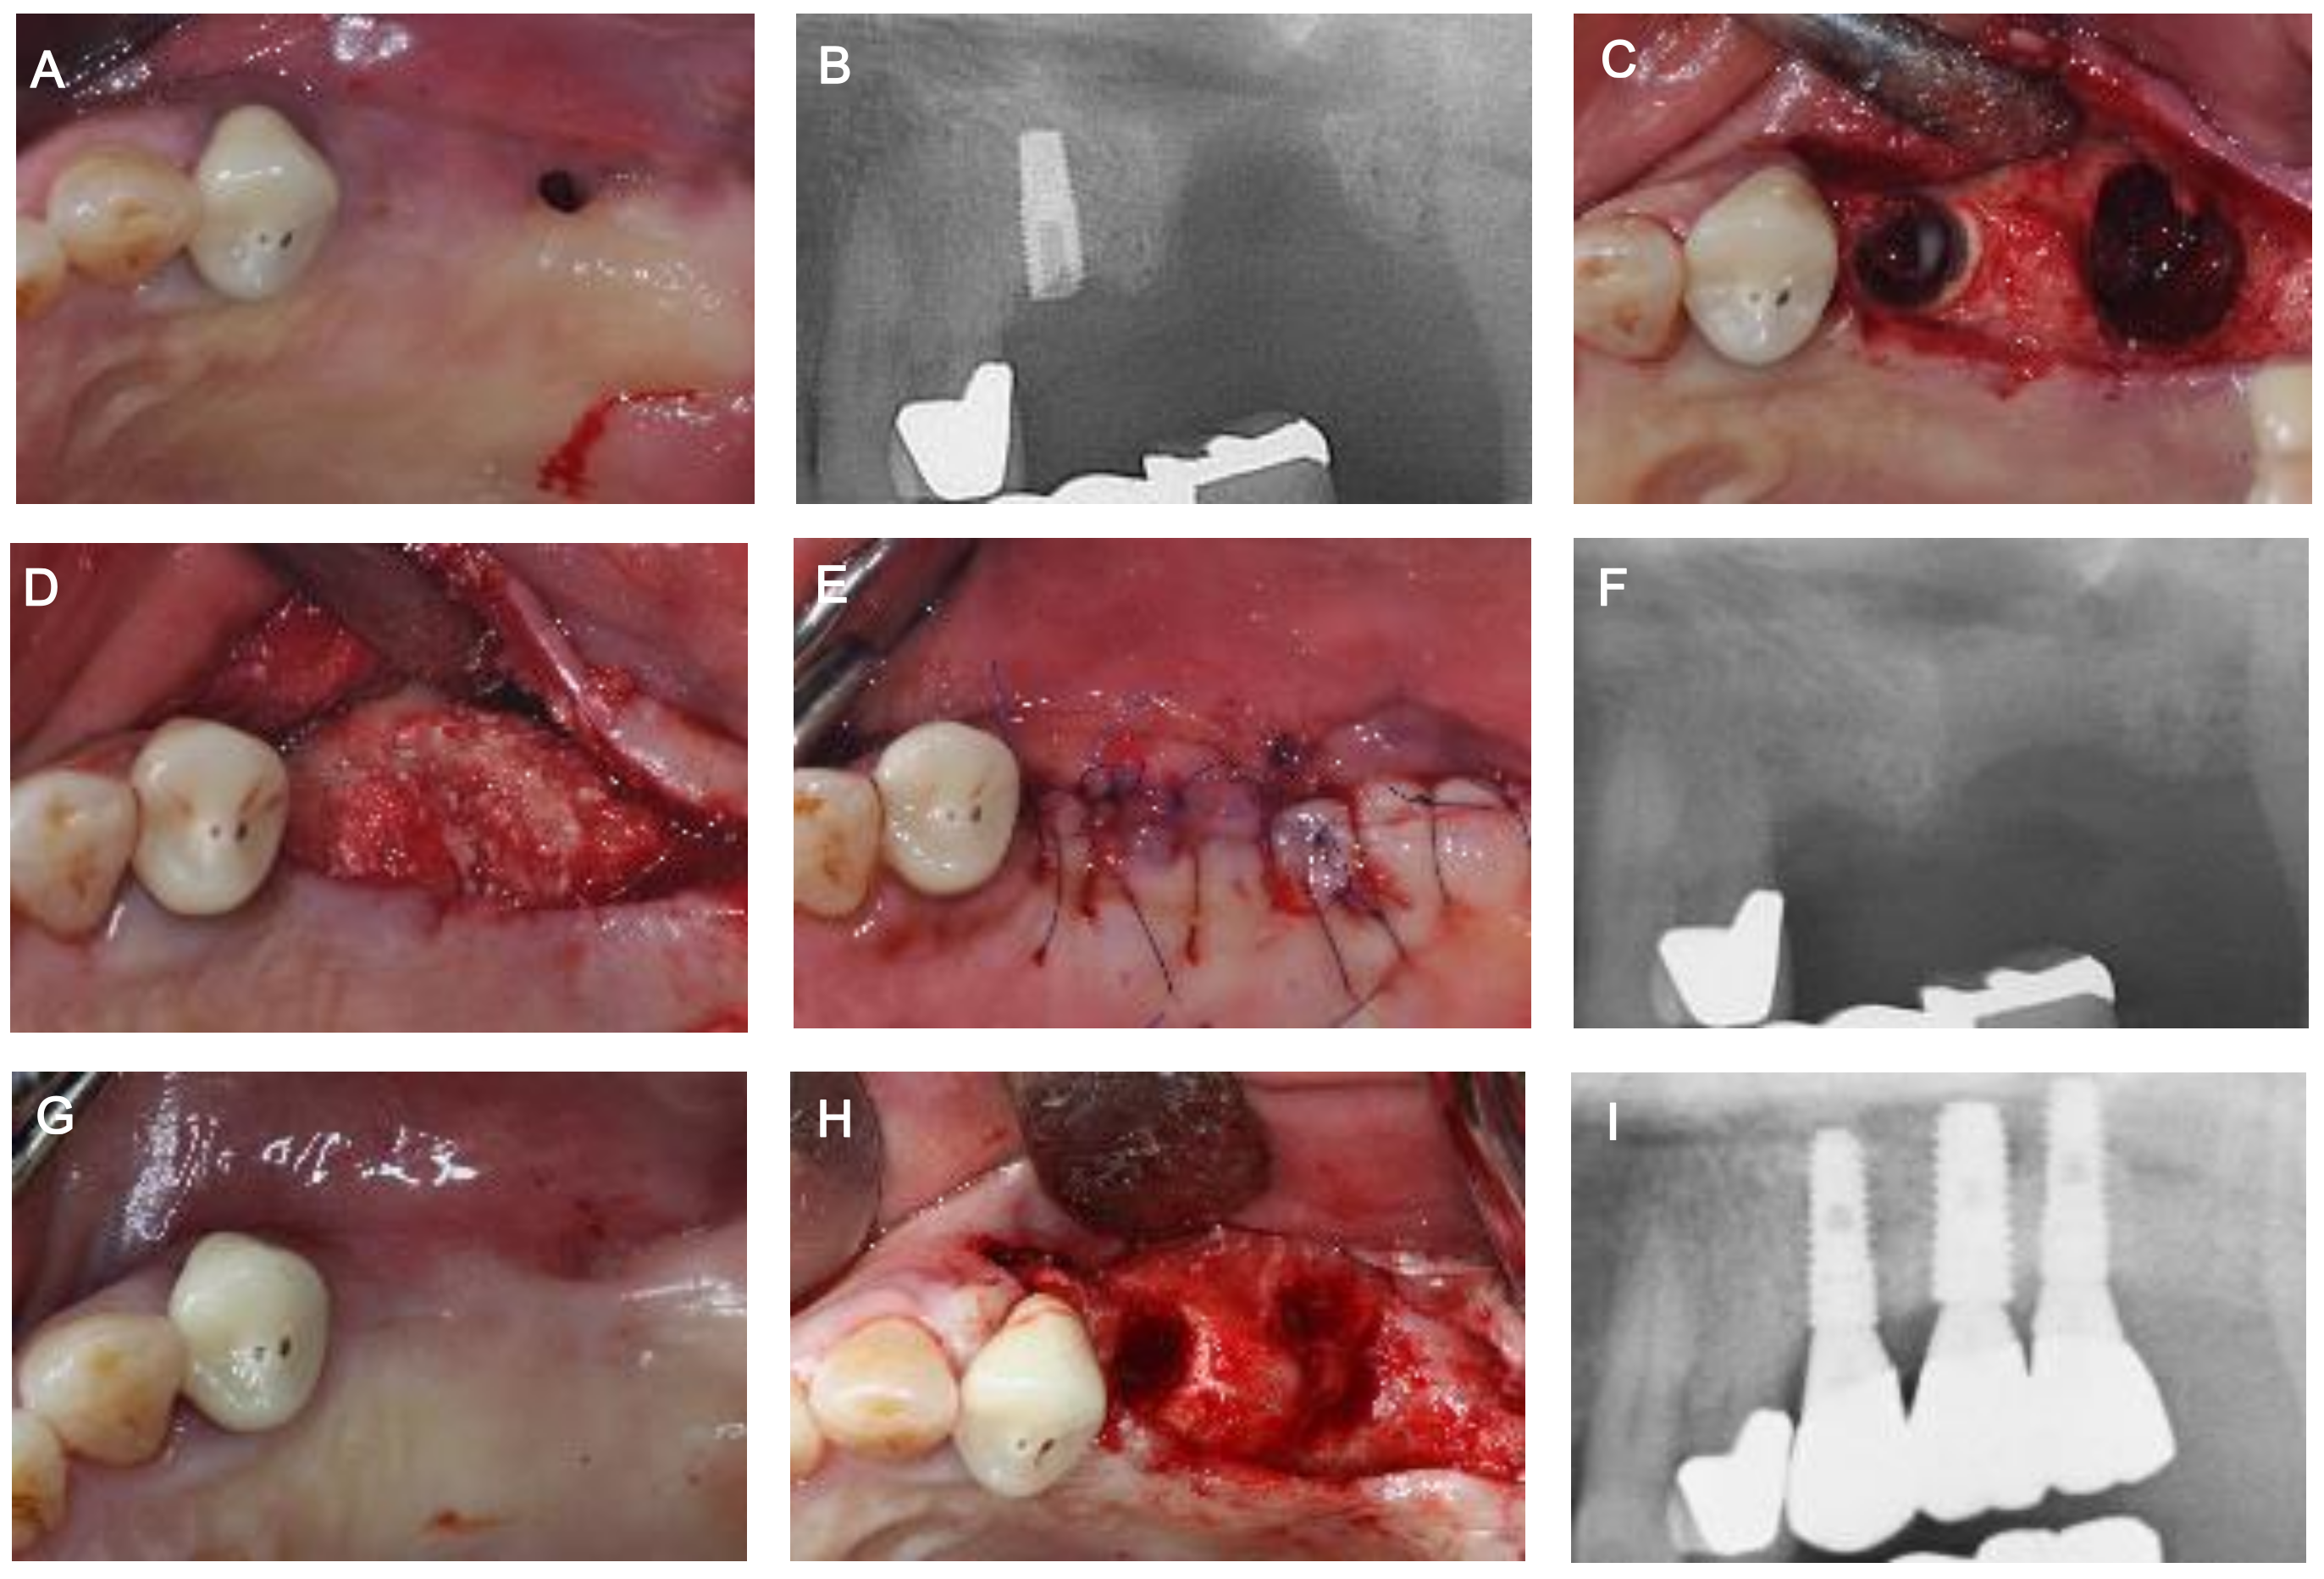

Implant Placement after Closure of Oroantral Communication by Sinus Bone Graft Using a Collagen Barrier Membrane in the Shape of a Pouch: A Case Report and Review of the Literature

2. Case Description